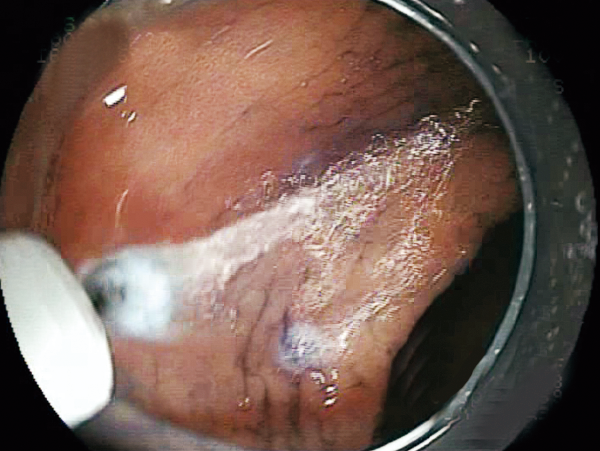

Clinical Image :Marking

Clinical Image :Water jet

Clinical Image :Mucosal Injection

Clinical Image :Submucosal dissection

Clinical Image :Submocosal injection

Clinical Image :Coagulation